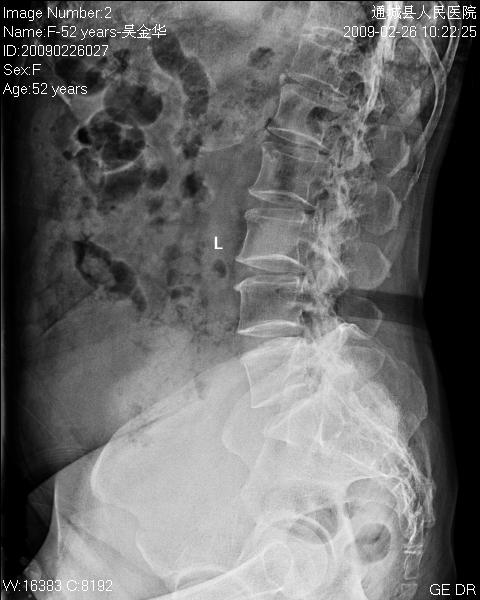

女性,52岁,腰痛二年余。

临床诊断:腰椎退行变。

平片仅能提示退变

1)腰椎退行改变。2)考虑盆腔巨大占位性病变;建议行进一步检查。

1)腰椎退行改变。2)考虑腹盆腔巨大占位性病变(其大部边缘清楚)考虑:来源于卵巢占位性病变可能,建议mri检查.

1)腰椎退行改变。

2)腹盆腔巨大占位性病变,来源于附件占位性病变可能,

3)左肾影不清,与腹腔盆腔占位病变有否联系?异位肾?

意见:请予mru检查,如果无mri机器,请予ivp,或ct扫描重建。

退变,下腹部椭圆形密度增高影是什么呀?建议行ct检查一下。